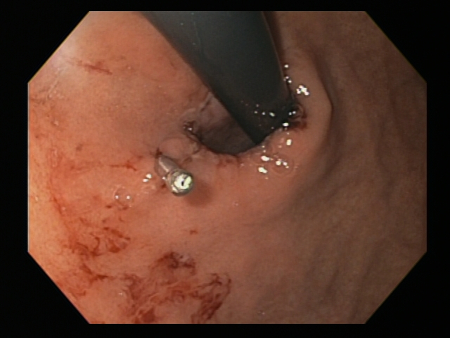

A chronic cough may be associated with whooping cough, bronchitis, bronchiectasis, emphysema, chronic obstructive pulmonary disease, or lung cancer.[25][Figure caption and citation for the preceding image starts]: Bleeding Mallory Weiss Tear viewed on retroflexionFrom the personal collection of Douglas Adler; used with permission [Citation ends].

[Figure caption and citation for the preceding image starts]: Bleeding Mallory Weiss Tear viewed on retroflexionFrom the personal collection of Douglas Adler; used with permission [Citation ends].